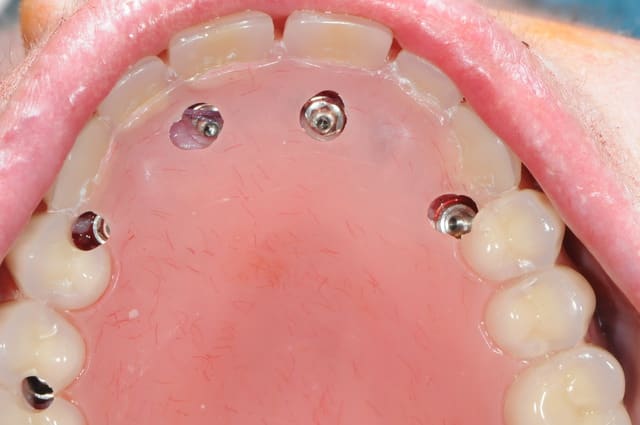

la patiente a été opérée hier et j'ai mis ses prothèses aujourd'hui.

la veille de l'intervention j'ai imprimé le model 3 D.